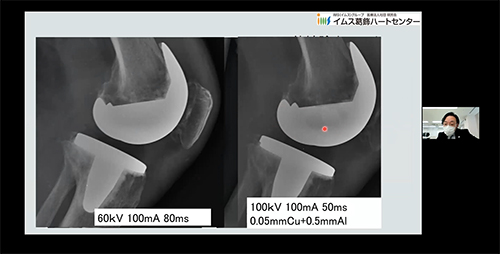

本年度入職した46名の診療放射線技師を対象に、『IMS放射線部 新人研修会 冬』を開催しました。感染対策状況を鑑み急遽Webでの開催となりましたが講師の工夫と参加者の熱意から充実した研修会となったと思います。その内容は、「一般撮影概論 画像の良し悪しの判断、撮影条件」「被ばく管理 放射線管理の観点から」を行い、診療放射線技師として理解するべき内容でありました。